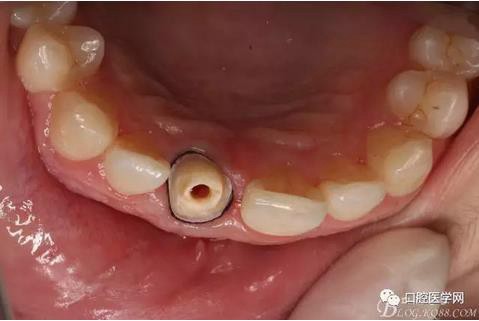

術(shù)前口內(nèi)照,11殘根,唇側(cè)牙齦紅腫,肩臺(tái)在齦下2毫米,舌側(cè)正常.21有被動(dòng)萌出,長(zhǎng)寬比例不協(xié)調(diào)。口腔衛(wèi)生一般,有菌斑。